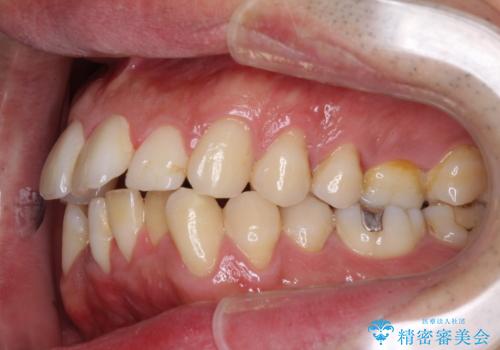

下顎骨が顕著に右側にずれている インビザラインによる咬合改善

下顎骨が顕著な左右差を持って成長したため、右側にずれている状態でした。

この方は元々骨格的な偏位が大きかったためか、治療中に下顎骨が上顎骨よりも右外側に誘導されて、右側の奥歯が全く咬合しない状態が続いてしまいました。